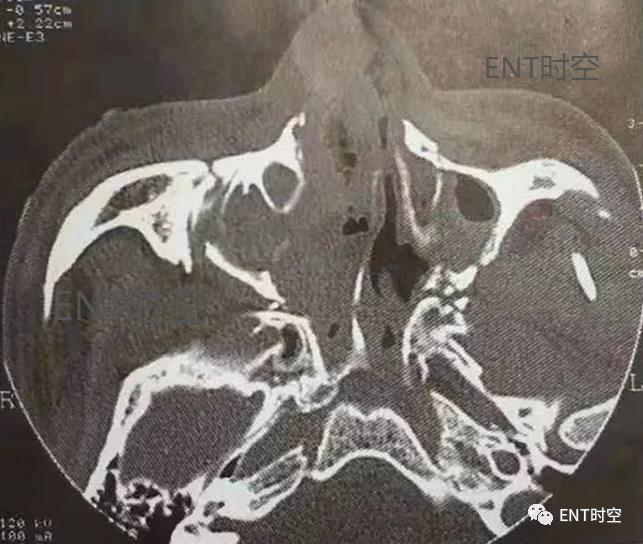

视神经管由蝶骨小翼的2个根及蝶窦的外顶壁围成,部分患者后筛窦外侧壁也参与视神经管内壁的构成。所以,外伤后骨折累及蝶骨小翼或蝶窦外顶壁时,即可造成视神经管骨折。CT表现为视神经管骨质中断移位,视神经管变形及继发蝶窦内黏膜增厚或积血。对视神经管骨折的诊断CT检查方法得当,一般不难作出明确诊断(图4)。

图4视神经管骨折(左侧)。轴位CT显示(箭头)视神经管内壁骨折。